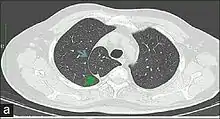

In human anatomy, an azygos lobe is a normal anatomical variation of the upper lobe of the right lung.[1] It is seen in 1% of the population. Embryologically, it arises from an anomalous lateral course of the azygos vein,[2] in a pleural septum within the apical segment of the right upper lobe or in other words an azygos lobe is formed when the right posterior cardinal vein, one of the precursors of the azygos vein, fails to migrate over the apex of the lung and penetrates it instead, carrying along two pleural layers that invaginates into the upper portion of the right upper lobe. As it has no bronchi, veins and arteries of its own or corresponding alteration in the segmental architecture of the lung, so it is not a true (misnomer), or even accessory, pulmonary lobe, but rather an anatomically separated part of the upper lobe.

An azygos lobe is usually an incidental finding on chest x-ray or CT scan, and is not associated with any morbidity.[3][4] However, it can cause technical problems in thoracoscopic procedures.[5]